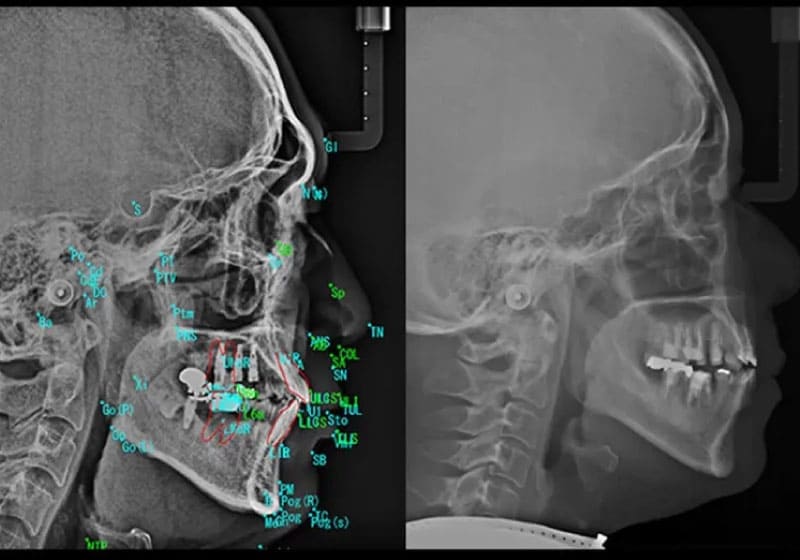

STEP 2

精密検査

レントゲンや口腔内の検査を行い、成長状態や歯並びを詳しく確認します。